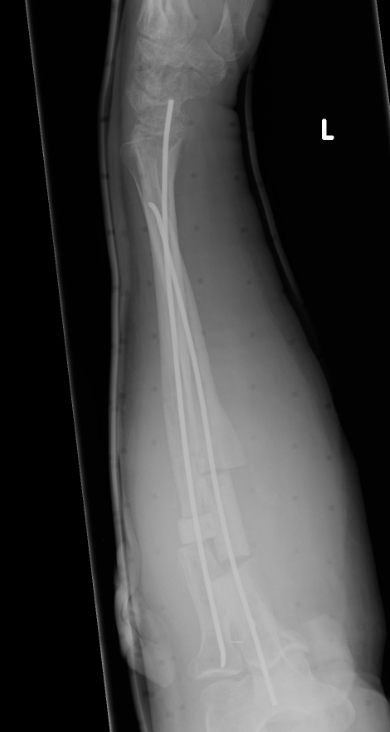

Intramedullary fixation

Results

Outcomes

- 30 BBFF fractures followed for 5 years

- supination / pronation 90%

- strength 70%